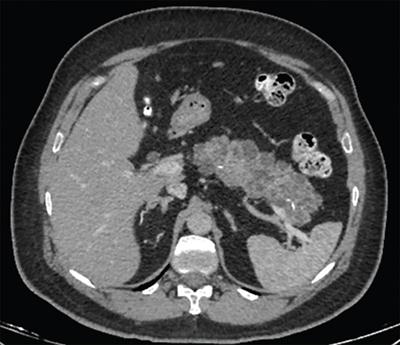

Image

Axial CT image shows pancreatic tissue (arrows) completely encircling the second part of the duodenum in patient with extramural annular pancreas.